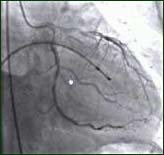

陈方:这是一位50岁的男性患者,原来患者没有任何症状,到医院是自己走来的,当时胸痛非常厉害,做心电图发现病人是急性下壁正后壁的心肌梗死,我们就决定从抢救室直接到导管室,来看一段录象,这是患者的右冠状动脉,发生了完全性的闭塞,患者的左冠状动脉的回旋支有90%的狭窄,前降支也有很多的不规则狭窄,当时我们决定把右冠状动脉打开放了两个支架,现在血管通了,患者最危险是在血管没有通时已经发生了三次心脏停跳,我们通过电击把病人抢救过来。每个人都只有三条冠状动脉血管,每根血管的直径为2-3毫米,通过这三条冠状动脉血管供应整个心脏,而心脏又关系着全身的血液供应,一旦这种供应被阻塞是很危险的。另外一个危险因素是突然阻塞后发生急性的缺血,缺血后患者就会发生室颤。